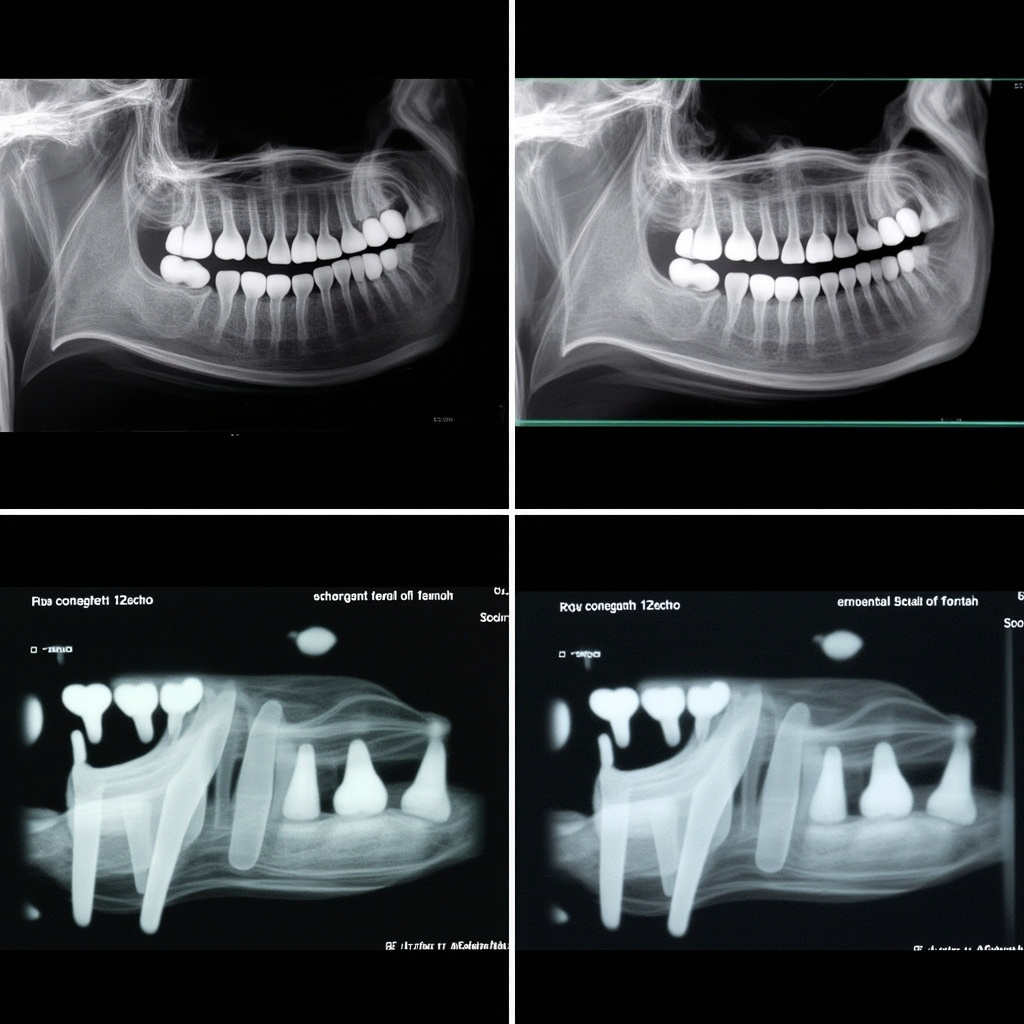

- Inconsistent Image Density: Images appear too light or dark despite consistent exposure settings

Dental X-ray systems are particularly sensitive to power fluctuations because they rely on precise voltage control for exposure parameter accuracy. When input voltage varies, the resulting kVp and mAs settings can deviate from intended values, directly affecting image quality and patient radiation dose.

Advanced diagnostics may require oscilloscope analysis to identify voltage waveform distortion, harmonic content, or transient spikes that can affect equipment operation. Power quality analyzers provide comprehensive data on voltage stability, frequency variations, and power factor measurements.